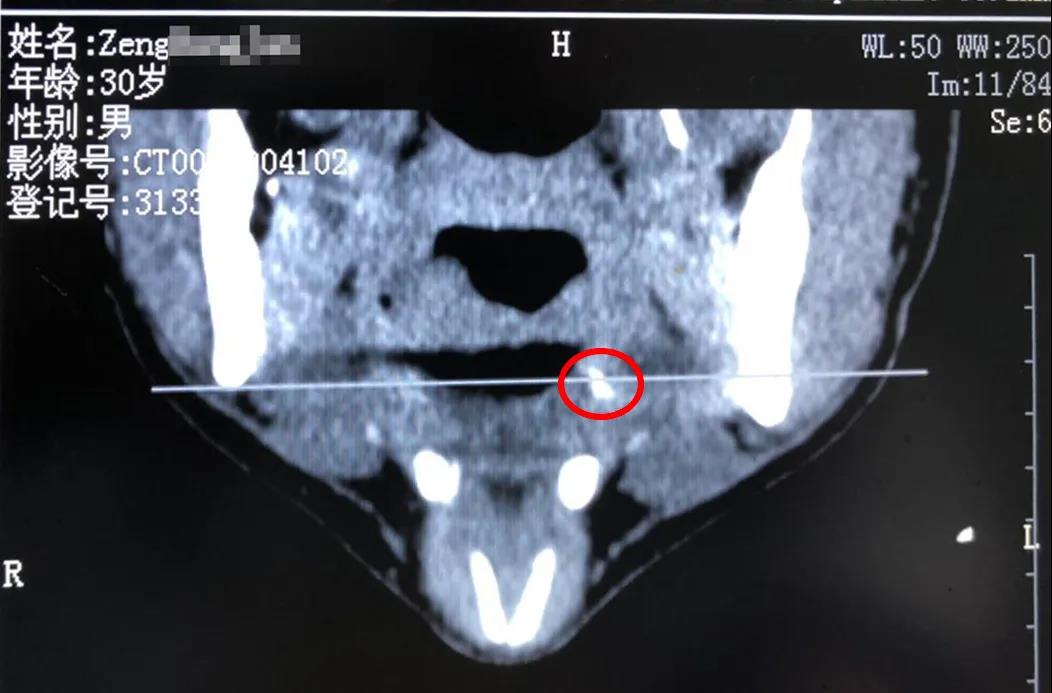

慢性咽炎治疗4个月后,男子上了手术台……